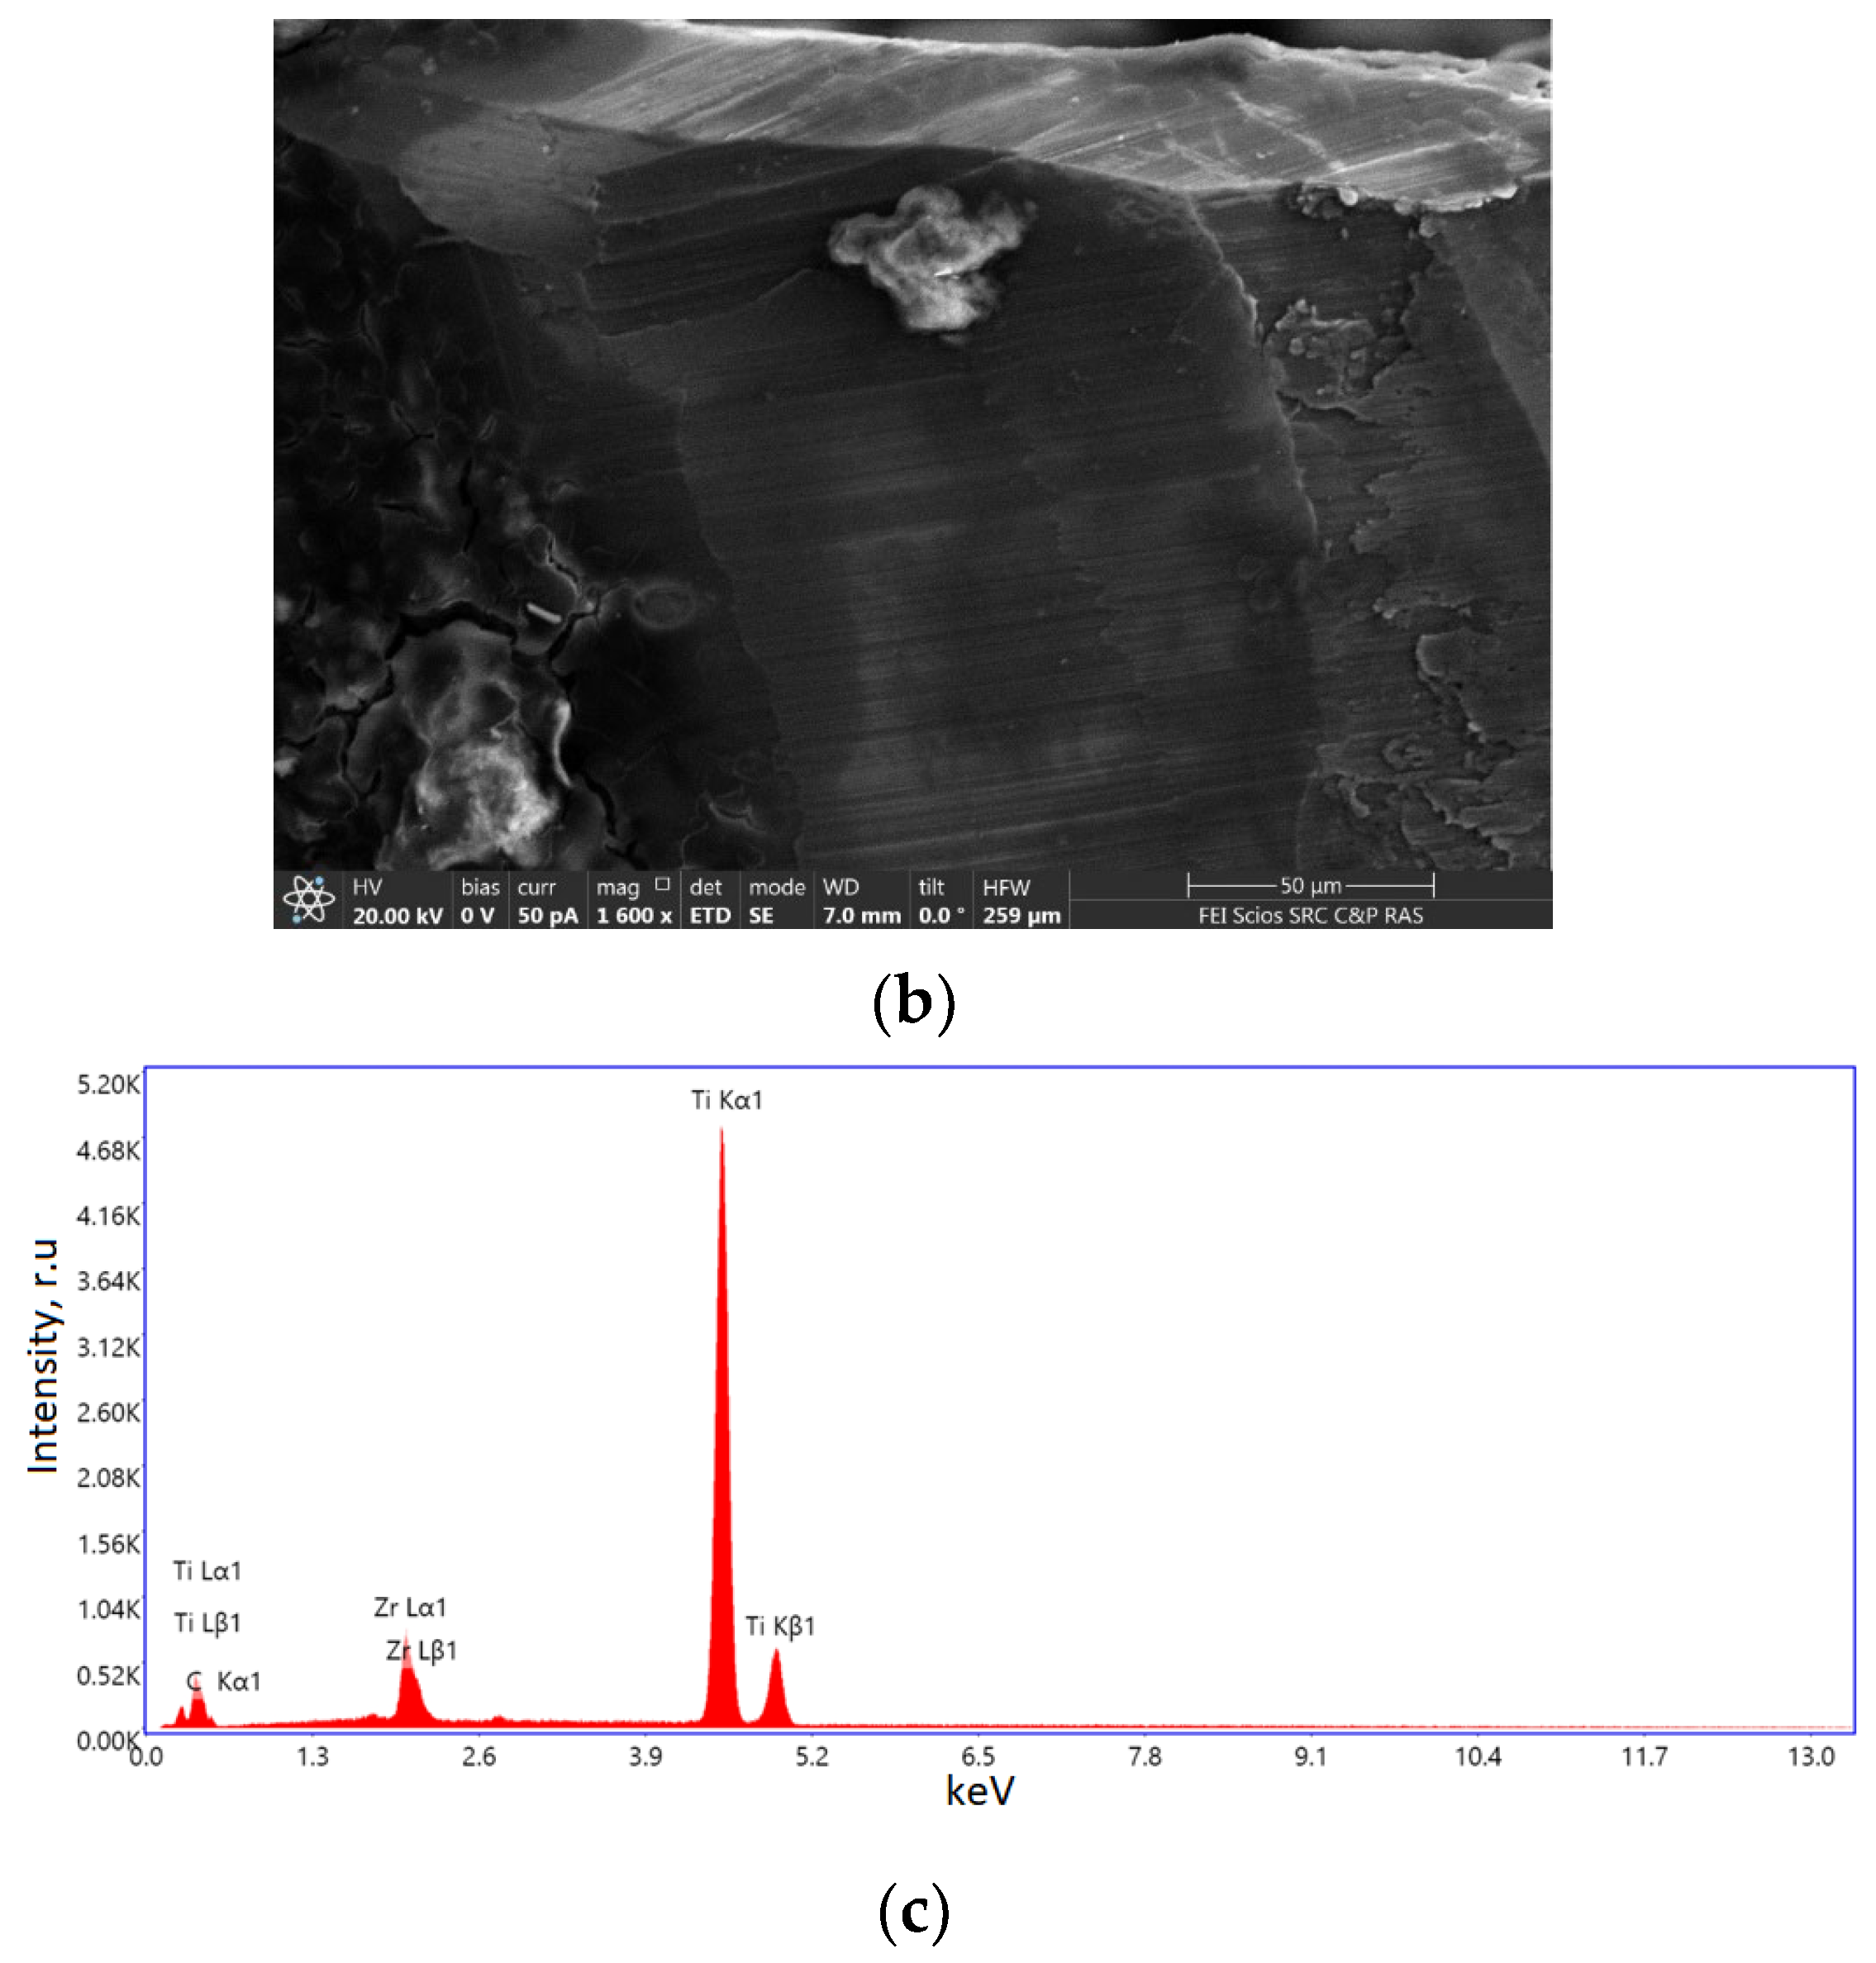

2.1.1. Results of X-ray and Electron Microscopic Studies

4.4. Methods of Scanning Electron Microscopy (SEM) and Transmission Electron Microscopy (TEM) with Energy Dispersive (ED) Analysis